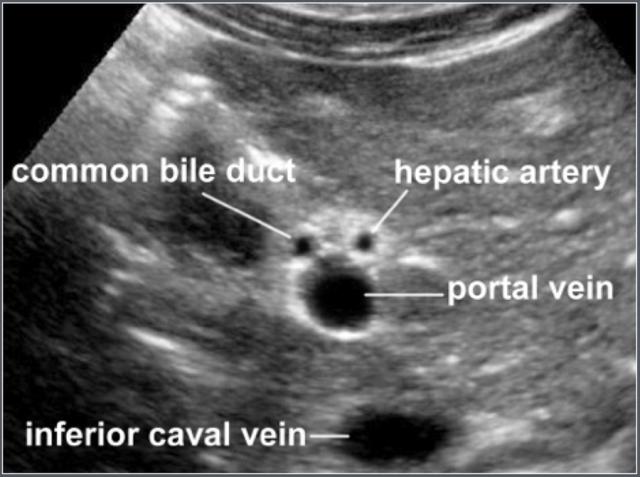

Hình ảnh

Hình ảnh siêu âm cắt ngang ống mật chủ và các cấu trúc giải phẫu xung quanh.